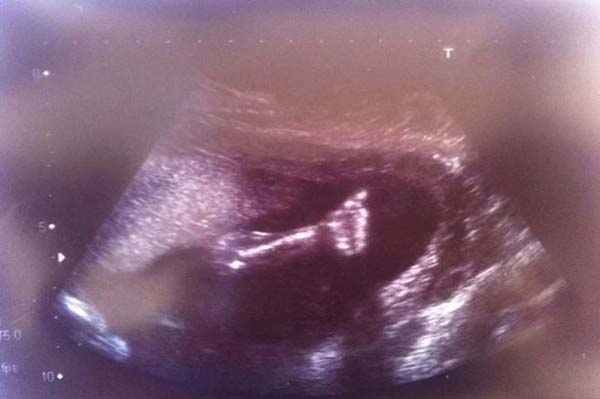

Az alábbi kép még a terhesség alatt készült, amelyen tisztán látható, hogy a pocaklakó feltartja a hüvelykujját, jelezvén: nem fogja feladni a küzdelmet, harcolni fog az életéért.

Az orvosok arról tájékoztatták a szülőket, hogy a műtét sikeres kimenetelére kb. 50 % esélyt látnak, és lehet, hogy egy műtét nem is lesz elég. Amikor azonban a kisbaba először mozdult meg édesanyja hasában, az már tudta: nem fogja feladni.

A kis Chanel Murris szerencsésen a világra jött, ám születése után azonnal súlyos szívműtét várt rá, ugyanis szívecskéjének csak az egyik fele dobogott. Az orvosok tehát neki láttak az életmentő műtétnek, és a 3100 grammos újszülöttet azonnal megoperálták.